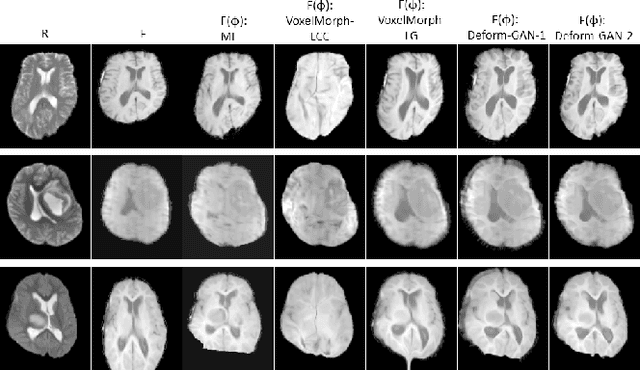

Abstract:Deformable registration is one of the most challenging task in the field of medical image analysis, especially for the alignment between different sequences and modalities. In this paper, a non-rigid registration method is proposed for 3D medical images leveraging unsupervised learning. To the best of our knowledge, this is the first attempt to introduce gradient loss into deep-learning-based registration. The proposed gradient loss is robust across sequences and modals for large deformation. Besides, adversarial learning approach is used to transfer multi-modal similarity to mono-modal similarity and improve the precision. Neither ground-truth nor manual labeling is required during training. We evaluated our network on a 3D brain registration task comprehensively. The experiments demonstrate that the proposed method can cope with the data which has non-functional intensity relations, noise and blur. Our approach outperforms other methods especially in accuracy and speed.